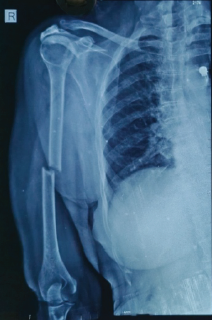

Atypical Transverse Midshaft Humerus Fracture in an Octogenarian: Surgical Nuances and Functional Outcome Following Locked Intramedullary Nailing

Jeff Walter Rajadurai OR , C S Likhit , Shailesh Kumar , K Purushothaman , D Sudharsan , Naveen Kumar Duraisamy

………………………………p.174-178